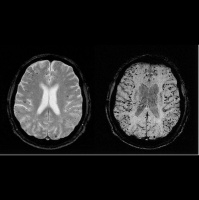

• The Alzheimer's Copernicus Problem, Part 1

22/10/2019 Duration: 46min

Almost six million people in the United States have been diagnosed with Alzheimer’s disease. And with baby boomers getting older, those numbers are only expected to rise. This disease, despite being studied by scientists for more than 100 years, has no cure. In our two-part series we first dive into the personal lives of the people at the heart of this disease: the patients and their caregivers. Then we uncover why effective treatments for Alzheimer’s lag so far behind those for cancer, heart disease, and HIV. It turns out that for all the decades researchers have been at war with the disease, they’ve also been at war with each other. Credits Hosts: Alexis Pedrick  Reporter: Rigoberto Hernandez Producer: Rigoberto Hernandez Senior Producer: Mariel CarrAudio Engineer: James Morrison Music courtesy of the Audio Network. These songs were used courtesy of Blue Dot Sessions:  "Kalsted,""Stretch of Lonely," "Thin Passage," "Waltz and Fury," "Dash and Slope," "Gilroy Solo," 'House of Grendel," "Uncertain Ground," an

• The Alzheimer’s Copernicus Problem, Part 2

22/10/2019 Duration: 42min